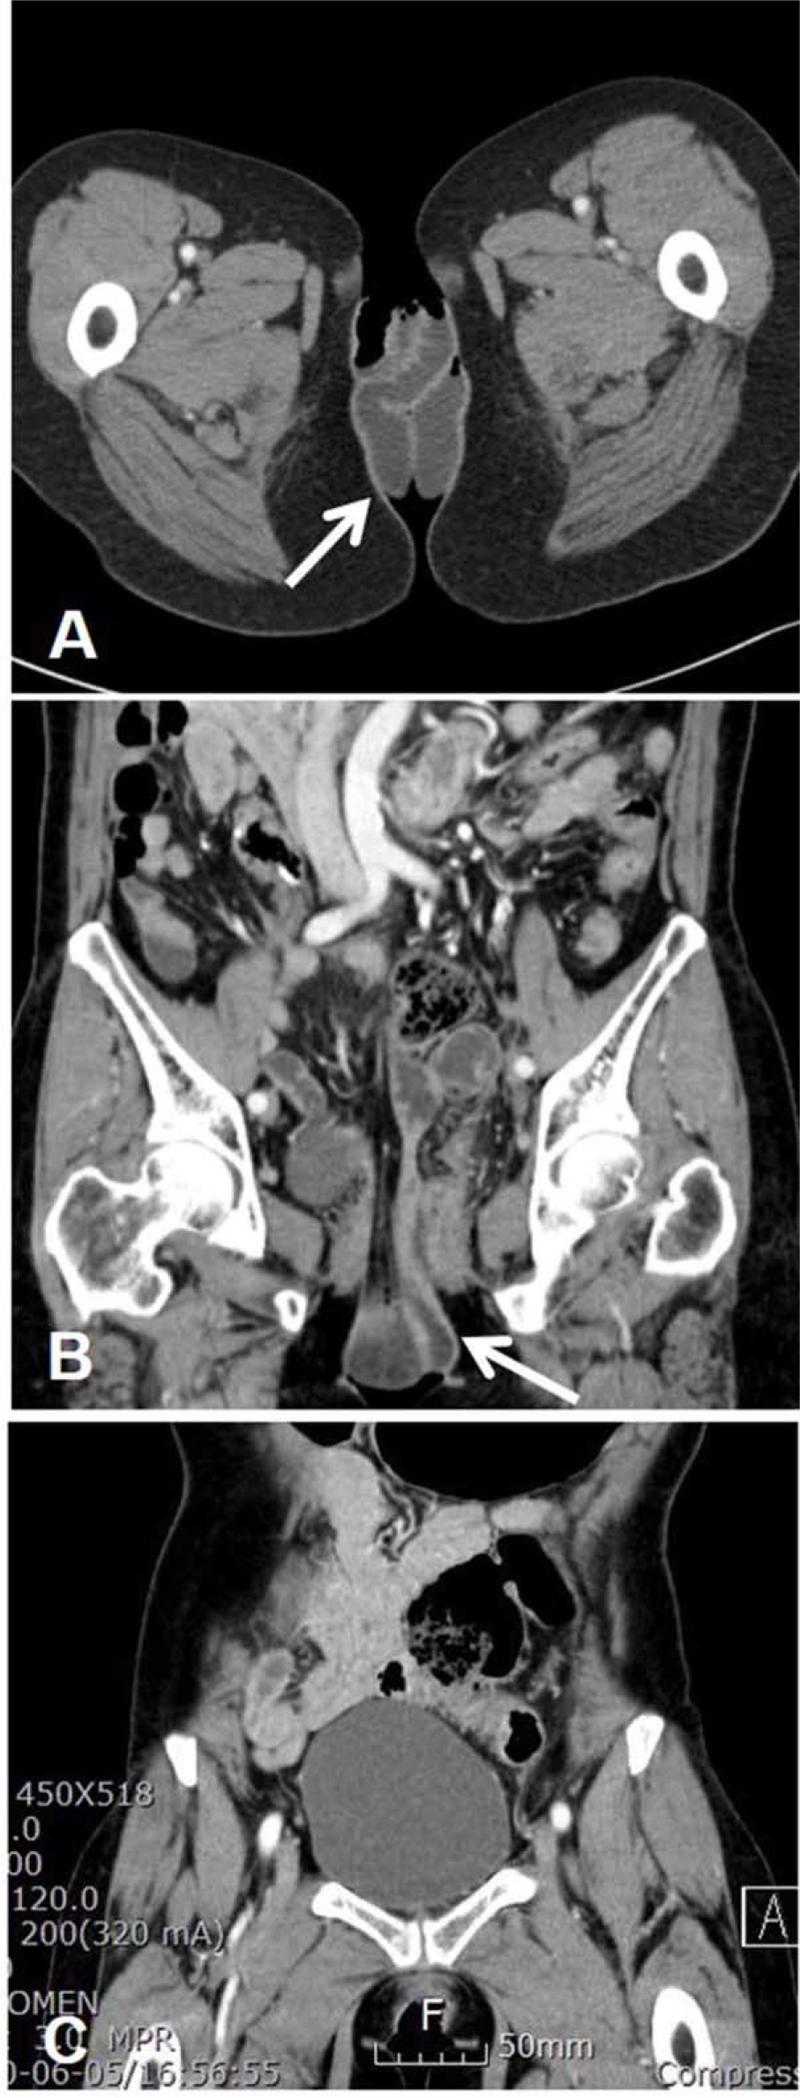

DIAGNOSIS

Pelvic examination revealed prolapsed small-bowel loops (18-20 cm in length). Pelvic computed tomography scan confirmed the presence of transvaginal evisceration of the small bowel.

盆腔检查显示小肠套叠(长 18-20cm)。盆腔 CT 扫描证实存在经阴道小肠脱出。